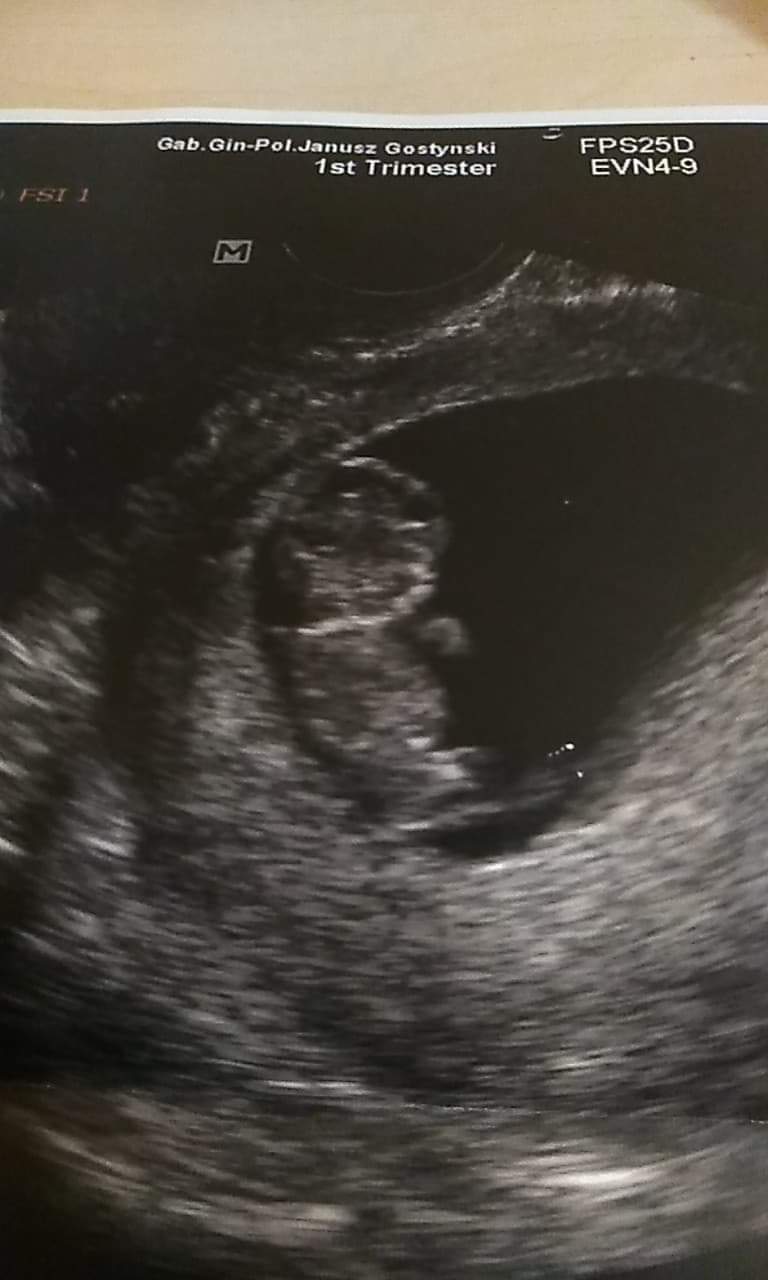

To moje maleństwo :-)

Załączniki

• received_400057177481536.jpeg

received_400057177481536.jpeg

54,9 KB · Wyświetleń: 209